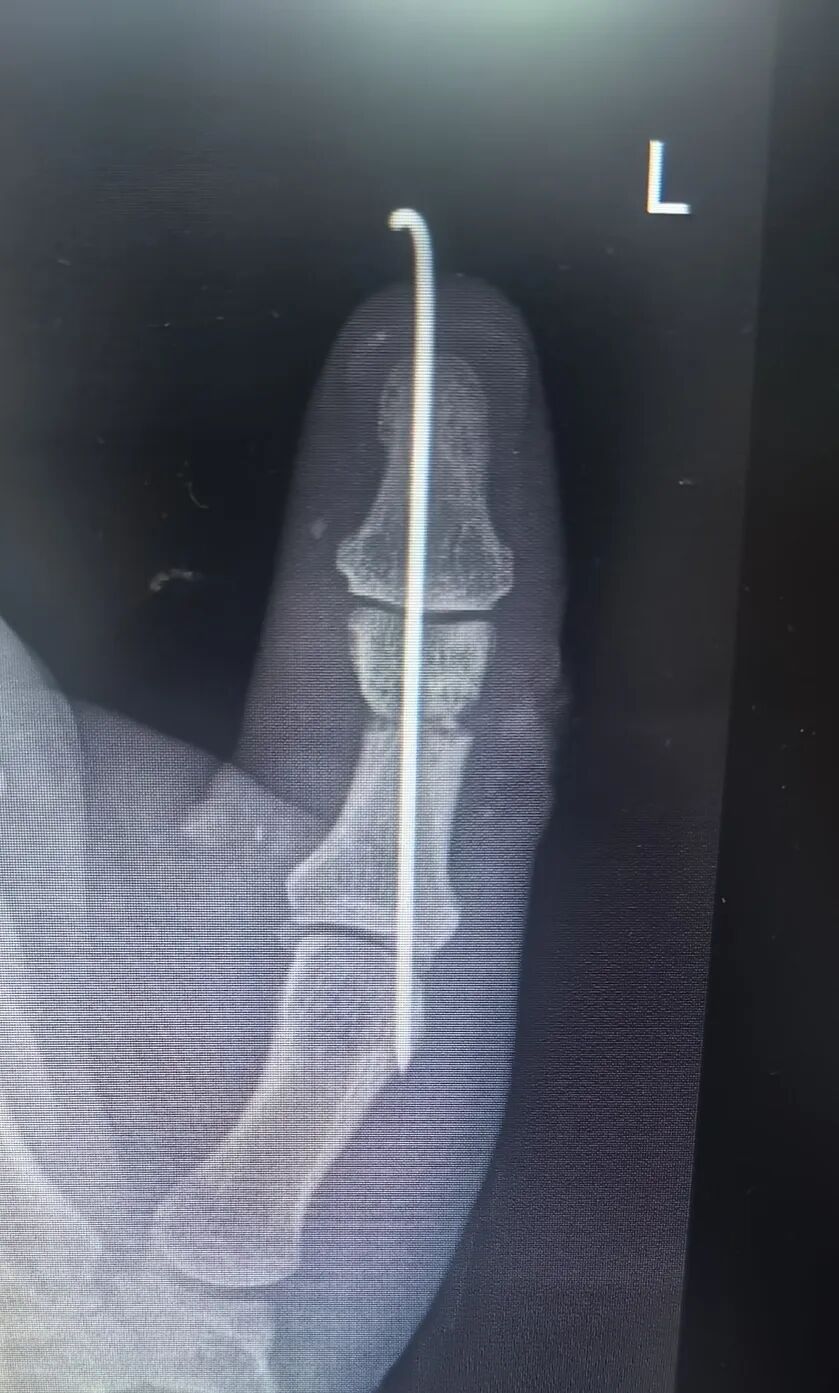

在剧痛中煎熬度过4天后,终于达到非洲,李先生第一时间被送往当地医院,在环境简陋的“手术室”完成了“左手拇指清创+指骨骨折内固定”。

向炜医生在晨交班上,结合患者的病史及相关辅助检查汇报了病情:“目前主要考虑左手拇指骨折术后感染,皮肤软组织情况差,很可能骨髓也已感染。若不及时控制,存在截指可能。”

向炜医生回忆术中情况也满是挑战:骨折固定位置奇特,伤口缝线粗大无比!此外不仅伤口感染重,坏死组织多,而且屈伸肌腱未修复,屈肌腱回缩未见,伸肌腱砸伤毁损;桡侧血管神经未修复;整个拇指仅靠尺侧指动脉及少许皮肤软组织相连,危在旦夕!